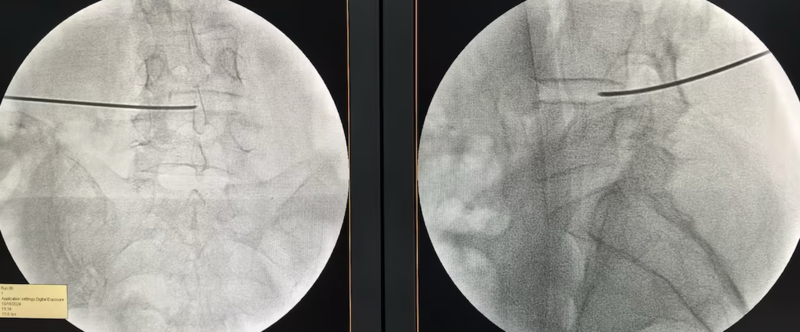

△射频消融技术治疗椎间盘源性腰痛

“我们采用椎间盘射频消融技术,具体来说就是用一根特制的直径只有1mm的细针扎到病变的椎间盘,通上微弱的电流,使病变的椎间盘气化达到减压的作用。”李强主任介绍。术后当天,赵女士就发现困扰多年的腰臀部疼痛消失了,出现喜极而泣的动人场面。她的外籍丈夫特意从国外赶过来致谢:“中国的技术让我们刮目相看。”